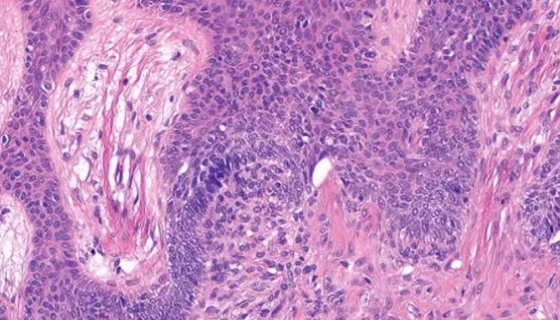

人喉表皮癌细胞复苏与冻存的处理方法有哪些?

人喉表皮癌细胞的运输和保存及复苏与冻存的处理方法有哪些?